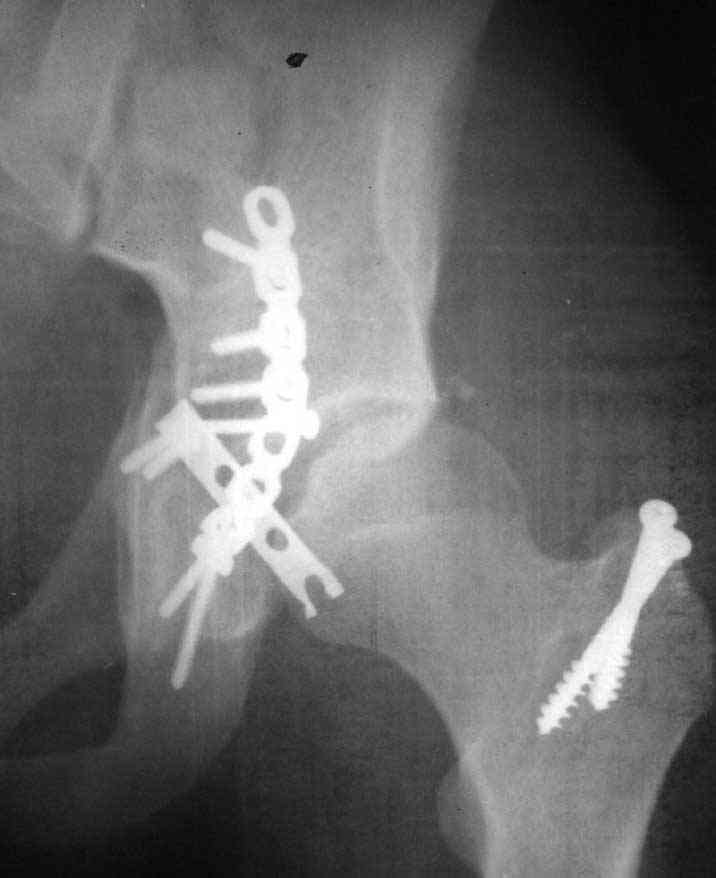

This is a 20 year old man who had an irreducible fracture dislocation of the left acetabulum, associated transverse + posterior wall type, operated nearly 2 weeks following the trauma.

Open reduction and internal fixation was performed through posterior approach with trochanteric osteotomy. Extraction of the incarcerated fragment was very difficult, and then reduction of the femoral head also felt less easy than usual. After plate fixation, the head was found to subluxe on maximum internal rotation. However, it became more or less stable after fixation of the trochanteric osteotomy and reattachment of the rotators. Xray showed lateral displacement of the femoral head. CT was also performed and it confirmed the lateral displacement although I don't know if it could be termed subluxation. The flexion- extension ROM is 0-45 with some internal-external rotation, but the limitation is mostly by pain. I cannot explain this situation and would you like to hear your suggestions.

I am confident that I left no intraarticular fragments. Could the comminution in the anterior wall visible on CT be responsible for this?

I am planning to fix his concomitant tibia fracture within 3 days, and in the process perform an examination under anaesthesia. If the ROM is good, I may leave him alone. What do you think? I am sending the x ray and CT in 3 mails